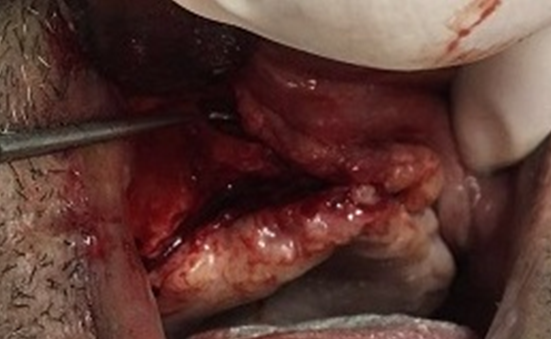

Durante o procedimento cirúrgico, inicialmente realizou-se infiltração anestésica com vasoconstritor por toda a região vestibular da maxila e palato visando reduzir o sangramento. A incisão foi realizada na crista do rebordo maxilar com duas incisões verticais relaxantes na região de segundos molares. Logo após, um retalho mucoperiostal foi rebatido expondo toda a região onde foram instalados os implantes. Toda a extensão da maxila foi exposta até a abertura piriforme, pilares caninos, zigomático e todo processo alveolar.

Para a remoção do implante na cavidade sinusal foi realizada uma pequena abertura na cavidade do seio maxilar para afastar a membrana sinusal, tentando manter sua integridade, e conseguimos pinçar o implante para removê-lo.